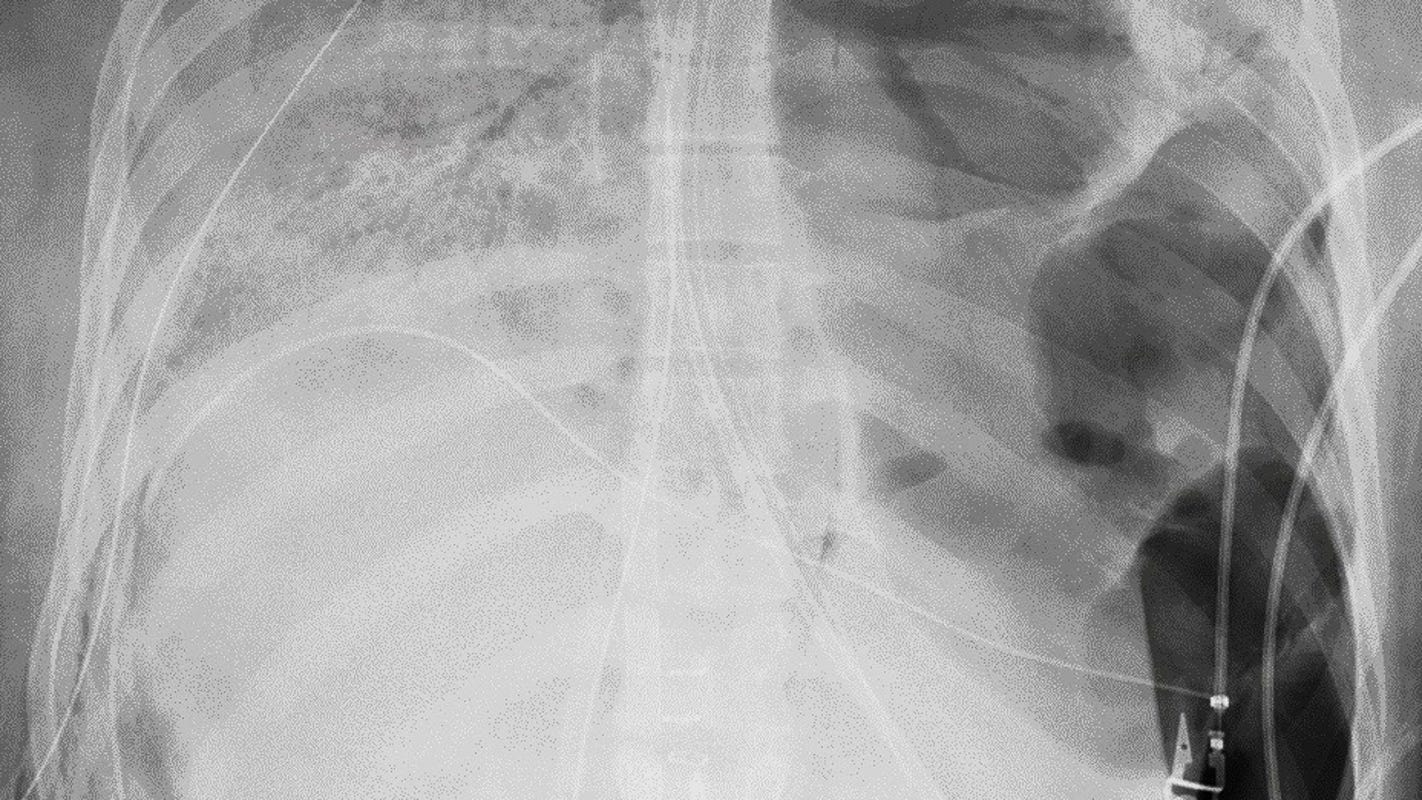

Remains of the Christopher Columbus statue near Little Italy in Baltimore after it was ripped from its pedestal by protesters on July 4, 2020.